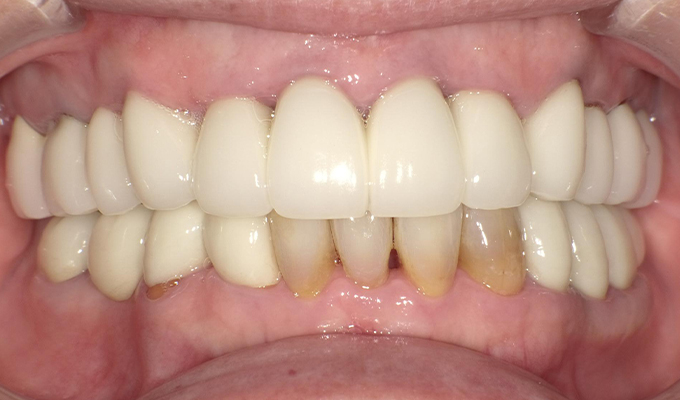

最新メンテナンス時(2024年)

保存が難しい歯を抜歯し、上はインプラント8本、下は奥歯にインプラント4本埋入しました。

補綴は変色しないメタルボンドを選択されたので治療完了して11年経過してもとてもきれいな状態で維持されています。